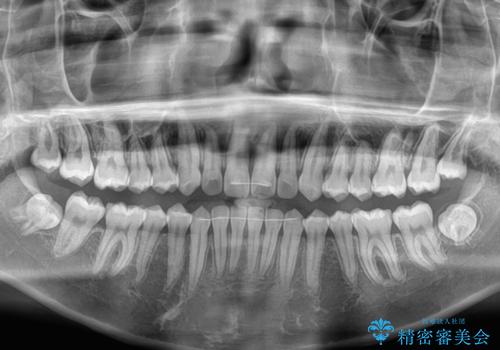

- 前歯の隙間を気にして来院された患者様です。

口元の突出感があり、小臼歯4本を抜歯して口元を引っ込める矯正治療も提案しましたが、本人は口元の突出感は気になっていないとのことで、インビザラインにて隙間やデコボコを改善することとしました。

軽度の歯列不正であったため、廉価版のインビザライン・モデレートパッケージにて治療を終えることができました。